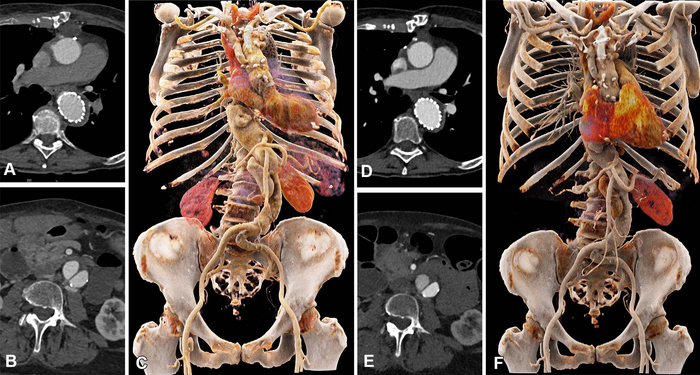

Comparison of image quality between EID CT with standard contrast media protocol and PCD CT with low-volume contrast media protocol using a matched radiation dose. Transverse and three-dimensional cinematic rendered images from thoracoabdominal CTA in a 71-year-old woman in group 2 are shown. (A–C) Images from third-generation EID CT with automated tube voltage selection of 90 kVp. (D–F) Images from PCD CT with reduced contrast media volume of 52.5 mL and VMI at 50 keV. Time interval between scans was 6 months. CTA = CT angiography, EID = energy-integrating detector, PCD = photon-counting detector, VMI = virtual monoenergetic images. Image courtesy of Radiological Society of North America

Photon-counting CT had a higher contrast-to-noise ratio, a key measure of image quality, which translates to a low-volume contrast media protocol. Contrast media volume was reduced by 25%.

Two independent readers rated the image quality of photon-counting CT as higher than that of conventional CT at an equal radiation dose.

“We showed that the improved image quality of CTA with photon-counting detector CT systems can be used to reduce the amount of administered contrast media to the patients, without reducing the diagnostic yield of the examination,” Dr. Alkadhi said. “Image quality remained at the same level as that of previous CT angiography examinations in the same patients using a conventional CT, despite the fact that we reduced the contrast media volume.”